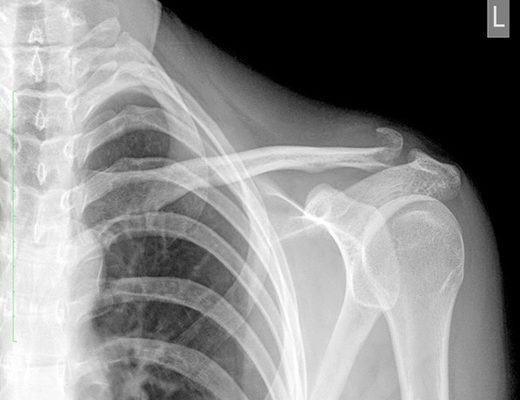

Однако внешний осмотр не дает информации о точном характере травмы, поэтому следует сделать рентген. В сложных случаях перелома ключицы со смещением может быть проведена компьютерная томография или магнитно-резонансная томография. Определение степени и характера смещения перелома, наличия или отсутствия разрыва связок и вывиха определяет варианты лечения.